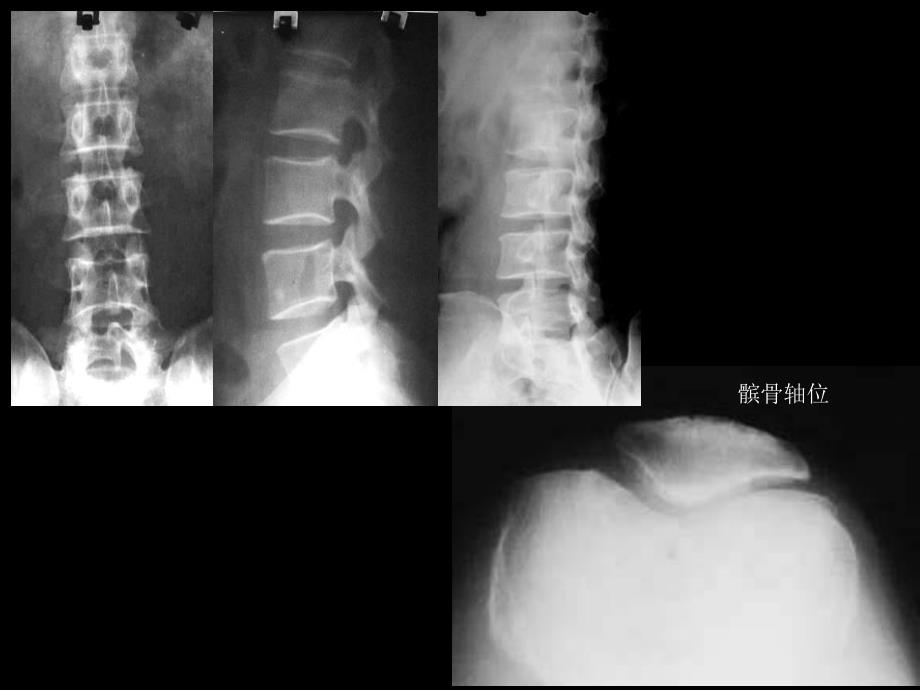

1、骨折及脱位移位判断l 以近端为准,判断远端移位方向和程度 l 移位和成角移位 骨折两端分离状况 成角 骨折两端长轴线平行状况l 良好的复位 对位 骨折端相接大于二分之一 对线 近端与远端长轴近似平行l 种类和检查方法左膝关节正位片l 影像学表现左膝关节正位片可见骨骺未闭合,股骨及腓骨骨质未见明显异常。左胫骨干骺端内侧可见背向关节生长的骨性突起,与骨干连续。l 初步诊断左胫骨干骺端内侧骨性突起,考虑外生骨软骨瘤。L髌骨轴位l 种类和检查方法左胫腓骨正侧位l 影像学表现左胫骨骨干下段见螺旋型透亮线,骨皮质连续性中断,断端移位和成角不明显。所见踝关节在位。腓骨骨质未见明显异常。l 初步诊断左胫骨下段

2、骨折。l 种类和检查方法右膝关节正侧位片l 影像学表现右胫骨近端见大片骨质密度降低区,破坏区近端达胫骨关节面下,远端有一定边界。病灶膨胀性生长不明显,局部骨皮质变薄。病灶内无钙化骨化表现。局部未见明显骨膜反应。周围软组织内未见肿块。l 初步诊断右胫骨近端骨质密度异常,考虑偏良性骨肿瘤,骨巨细胞瘤(溶骨型)或骨囊肿可能。R髌骨l 种类和检查方法腰椎正位片l 影像学表现腰椎正位片显示腰椎呈竹节样改变,棘突间呈骨性连接,腰骶关节间隙模糊。所见诸骨未见明显骨质破坏。l 初步诊断腰椎正位片示强直性脊柱炎改变,请结合临床。l 种类和检查方法颈椎侧位片l 影像学表现颈椎生理曲线欠自然,部分椎体(C6,C7)